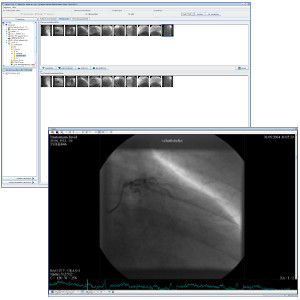

TM-PACS

TM-PACS ermöglicht die Komprimierung, Sicherung, Speicherung und Anzeige von radiologischen Bildern mit Betrachtung- und Visualiserungswerkzeugen (Zoom, Lupe, Annotation, Entfernungsmessung, Messdatenverfolgung usw.). Der Benutzer kann auch Koronarangiographie-Bilder, nuklearmedizinische PET-Bilder und klassischere Bilder (MRI, CT, Ultraschall usw.) anzeigen. Mit Hilfe von Labels, die mit den Studien verknüpft sind, können Studien gruppiert und mit einem einzigen Klick aufgerufen werden. Mit personalisierten Suchfunktionen kann die Krankenakte oder die gewünschte Studie sehr schnell gefunden werden. Die Ansicht ist für die Anzeige auf mehreren Bildschirmen optimiert. Die Integration mit der RIS- und PACS-Software, die auf den gleichen Befundworkstations installiert sind, wurde ebenfalls berücksichtigt.